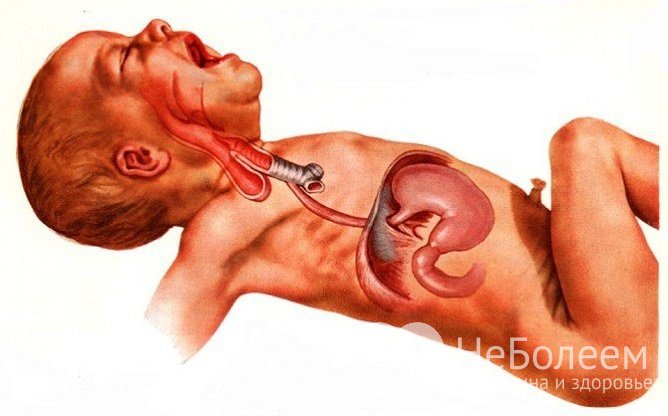

При атрезии пищевода слюна, слизь, пища попадает в дыхательные пути

При атрезии пищевода слюна, слизь, пища попадает в дыхательные путиПри кормлении новорожденного атрезия пищевода проявляется следующими признаками:

- моментальное срыгивание;

- рвота неизмененным молоком;

- тяжелый приступообразный кашель;

- удушье;

- акроцианоз;

- вздутие живота.